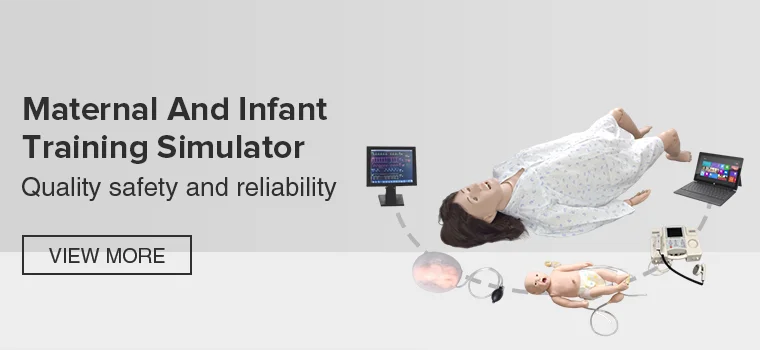

19YRSMain categories: Emergency training manikin,Physical examination training simulator,Nursing skills training simulator,Clinical skills training simulator,Maternal and infant training simulator